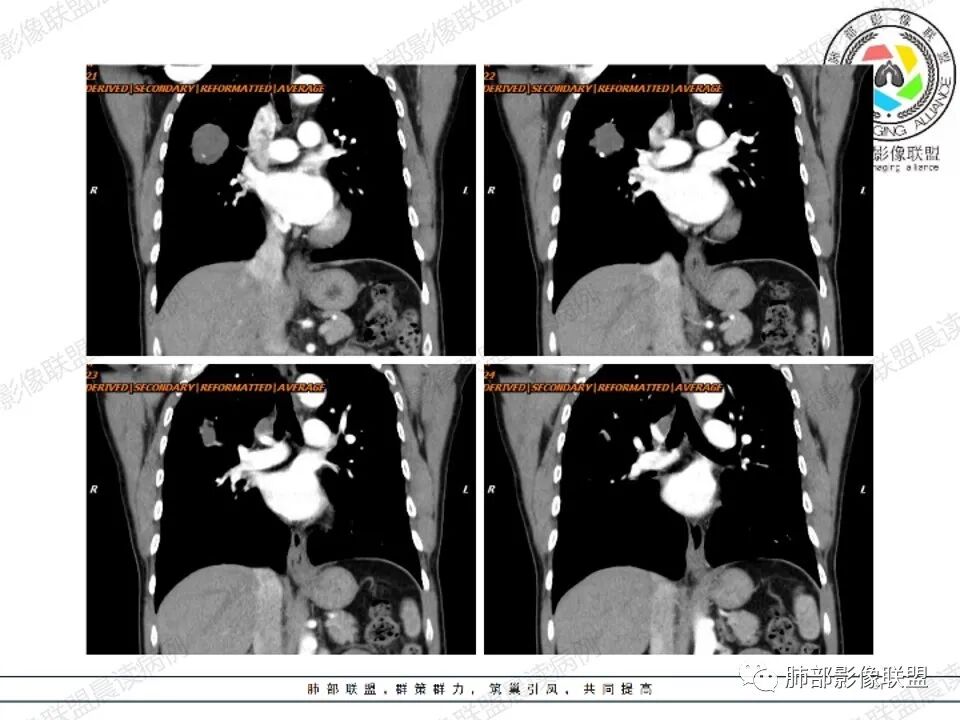

肺隔离症

1.肺隔离症也称为有异常动脉供血的肺囊肿症,是临床上相对多见的先天性肺发育畸形,为胚胎时期一部分肺组织与正常肺主体分离,单独发育并接受体循环动脉的异常动脉供血,所形成无呼吸功能囊性包块,这部分肺组织可与支气管相通,造成反复发作的感染,不相通时则不会出现呼吸道症状,多见于青少年,年龄在10-40岁。根据与正常肺有无共同胸膜覆盖分为叶内型和叶外型,叶外型罕见。

2.临床表现:叶内型大多数有呼吸道症状,容易伴发感染,如咳嗽、咳痰、发热、胸闷等;无症状主要发生于叶外型,早期叶内型病程与支气管不相通亦可无症状。

3.影像表现:常好发于下叶基底段,不规则团状、大片状软组织密度影及囊状低密度影,如合并感染可见液气平面,边缘模糊不清,增强扫描来自体循环的异常血供是关键,大多数来自降主动脉,病灶可见不规则强化。

左下肺囊性肿块---肺隔离症,由腹主动脉供血